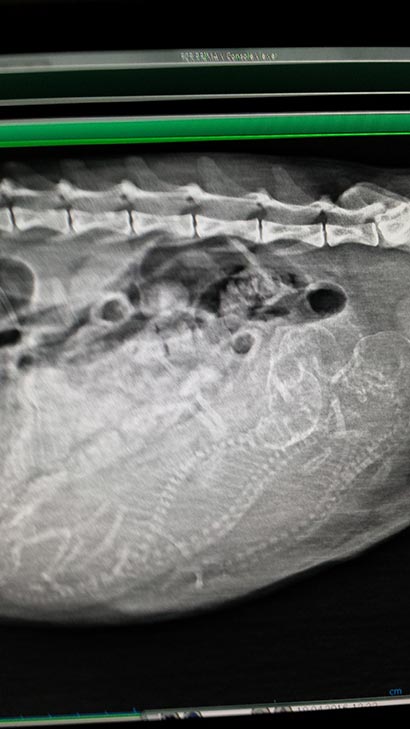

Da es Caline nicht sehr gut ging haben wir Sie in eine Tierklinik gebracht.

Dort hat sich herausgestellt das sie hochschwanger war. Die Kleinen mussten per Kaiserschnitt geholt werden, da die Gebärmutter so voll war und gegen den Magen gedrückt hat.

Da Caline keine Milch hat wurden die Kleinen erfolgreich einer anderen Mutterkatze "untergeschoben" . Caline hat noch eine Schnupfeninfektion und kann hoffentlich bald die Tierklinik verlassen. Über finanzielle Unterstützung würden wir uns sehr freuen. |